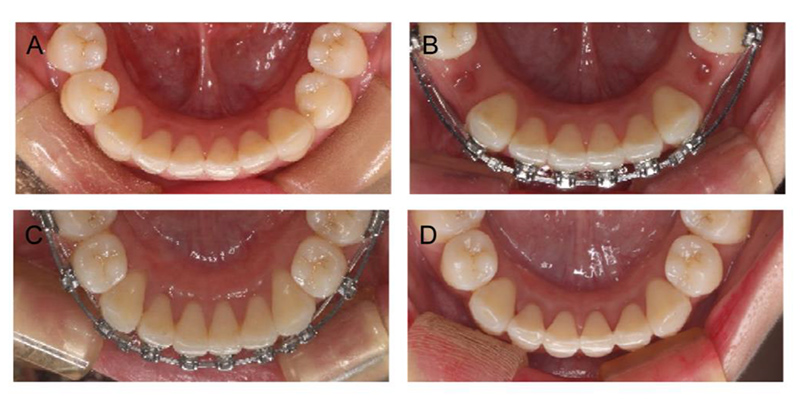

قبل و بعد ارتودنسی فک پایین

درمان ارتودنسی ممکن است برای اصلاح مشکلات فک پایین در شرایط خاص کافی باشد، در درجه اول زمانی که ناهماهنگی شدید نیست و شامل ناهماهنگیهای اسکلتی قابل توجهی نمیشود اما در ناهماهنگیهای قابل توجه اسکلتی زمانی که فک پایین به طور قابل توجهی در مقایسه با فک بالا بیرونزدگی یا عقبنشینی داشته باشد، باید هر دو فک تحت درمان قرار بگیرند.

در مواردی که فک پایین جلوتر یا عقبتر از حالت استاندارد قرار دارد، یا بههمریختگی دندانها فقط در فک پایین دیده میشود، همیشه نیازی به جراحی نیست. در بسیاری از این شرایط، میتوان با براکتهای ارتودنسی ثابت یا در صورت نامرتبی جزئی، با پلاکهای متحرک و الاینر شفاف، موقعیت دندانها را بهتدریج اصلاح کرد. این روشها نهتنها بدون جراحی انجام میشوند، بلکه یکی از بهترین گزینهها برای اصلاح ناهنجاریهای خفیف تا متوسط بهشمار میآیند.